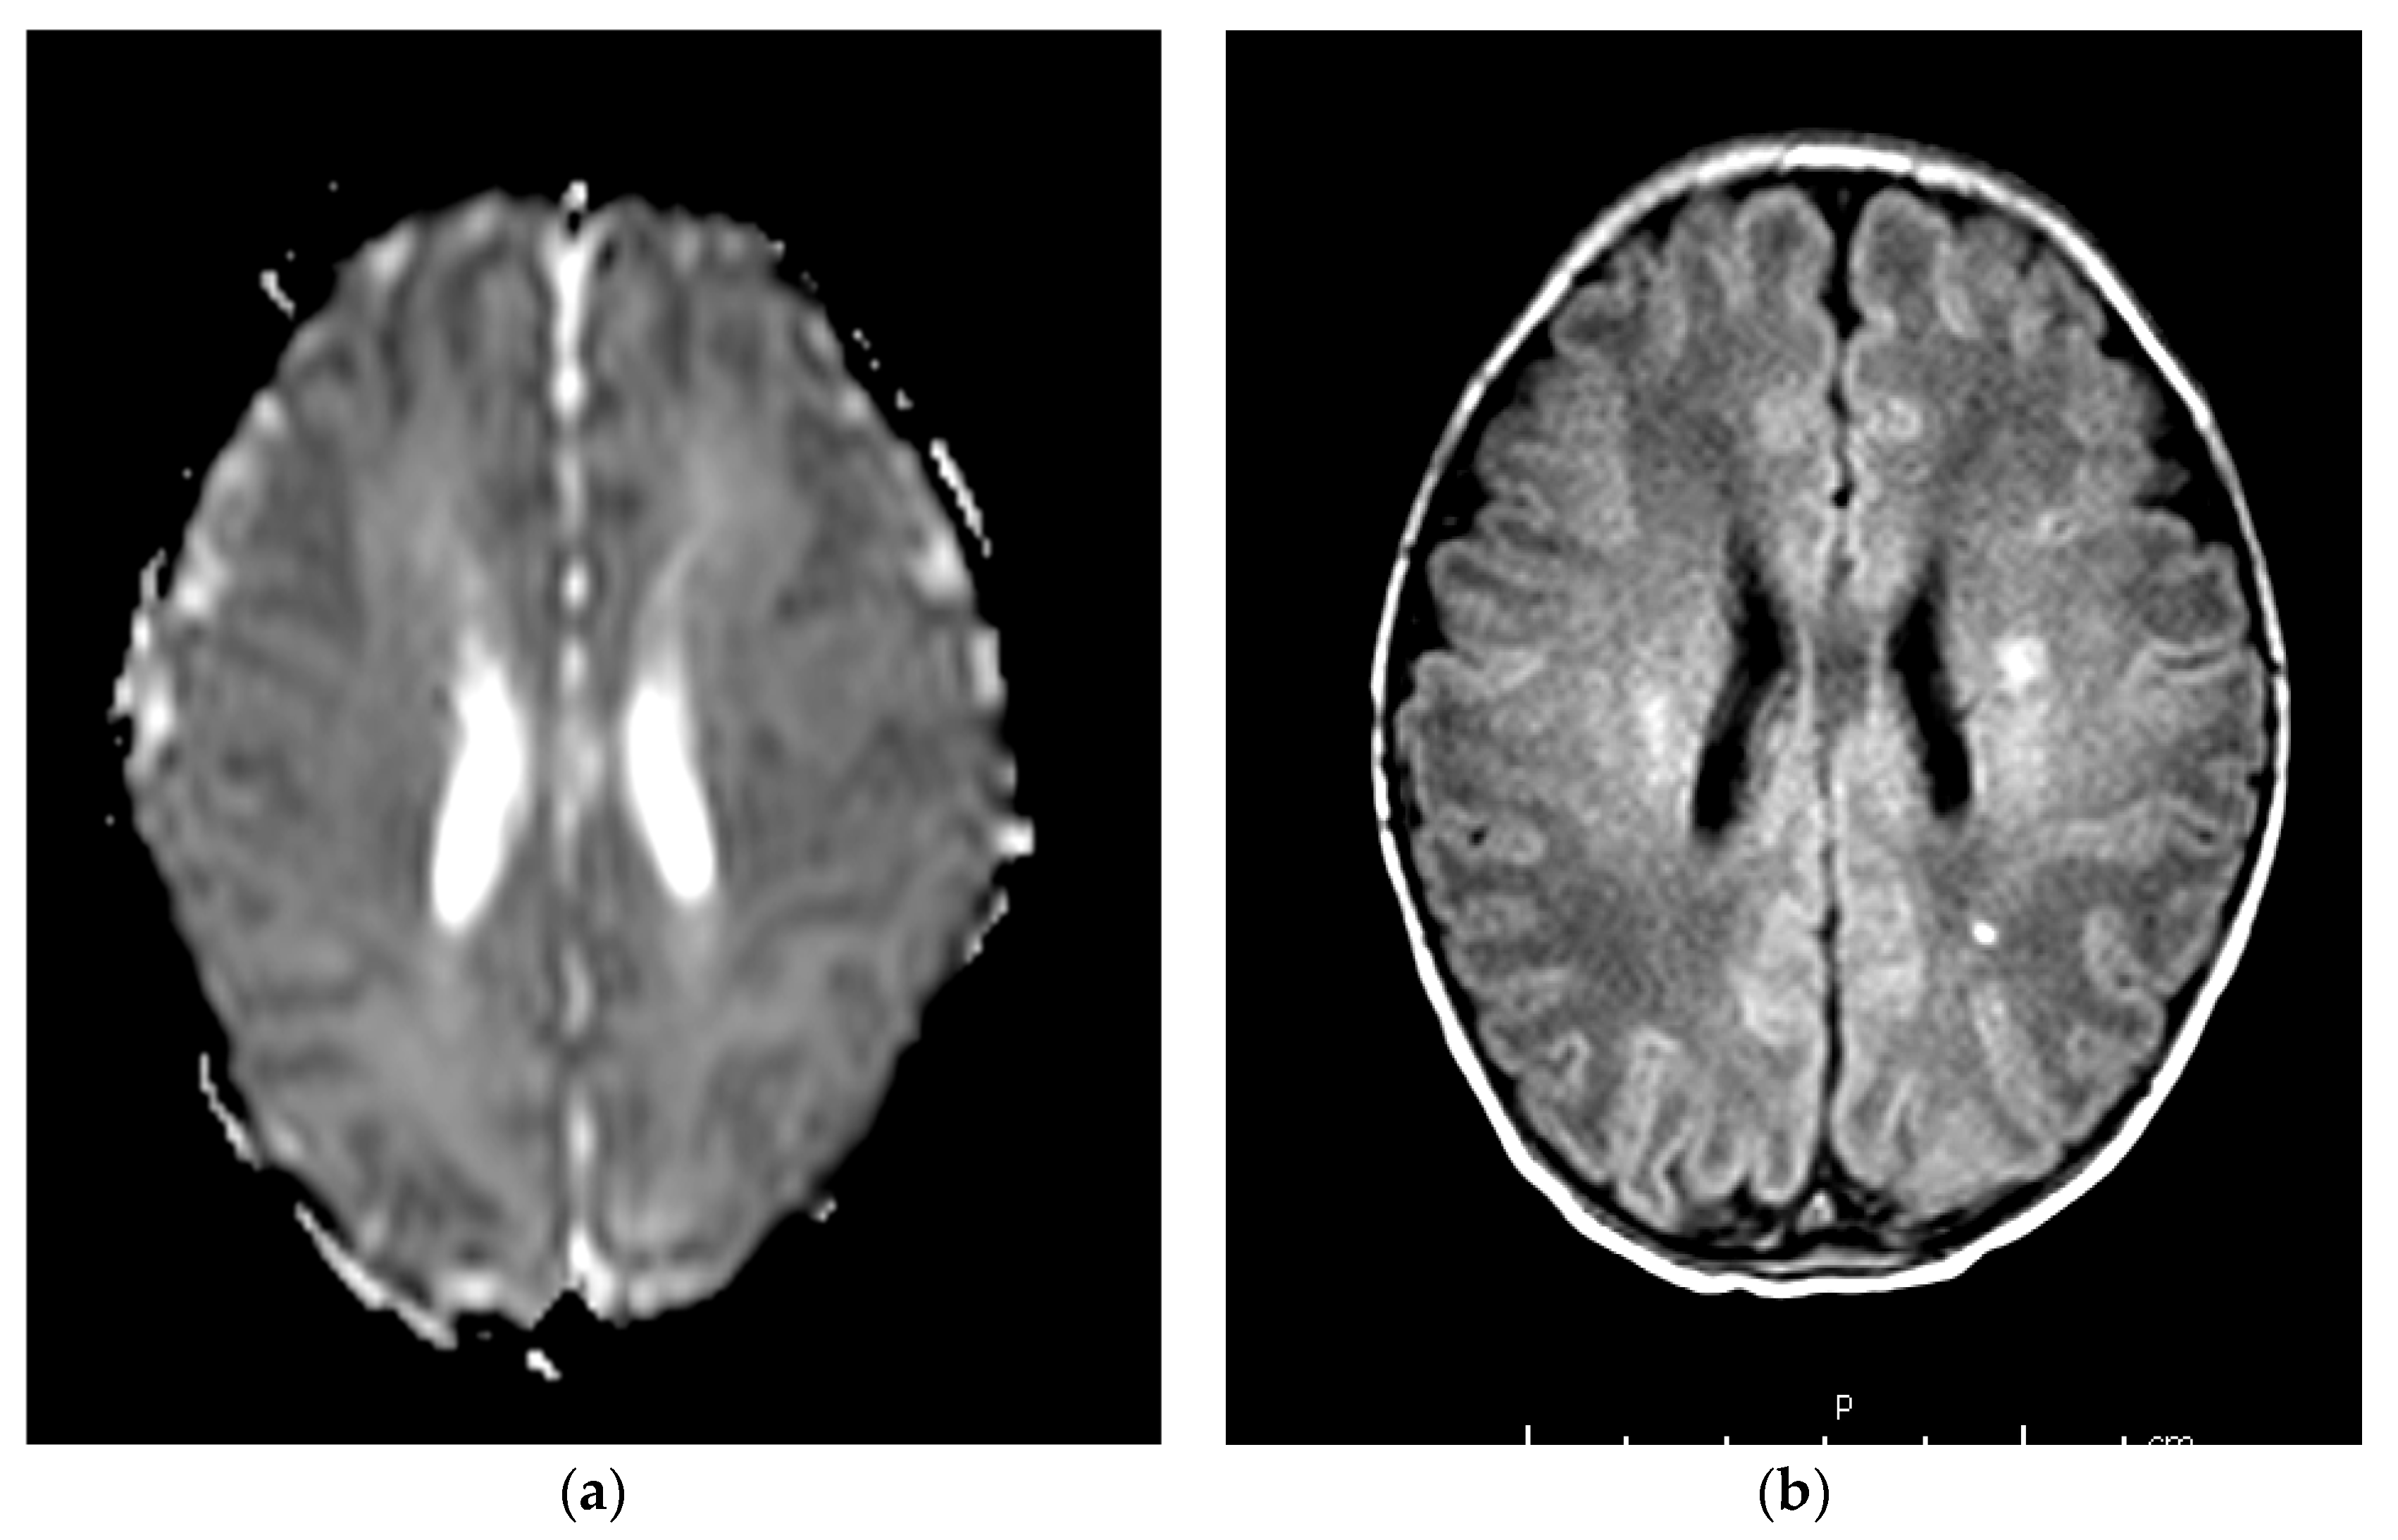

| 1 | 80 | CPR + OT | NR | NR | 3 | Severely abnormal | 7 | 59 | 5 | 28 | Severe lesions of basal ganglia and thalami | Spastic cerebral palsy | NA |

| 4 § | 140 | CPR + OT | 6.9 (−14) | 6.8 | 2 | Moderate abnormalities | 4 | 19 | 5 | 64 | Mild focal white matter lesions | Normal ¥ | 112 |